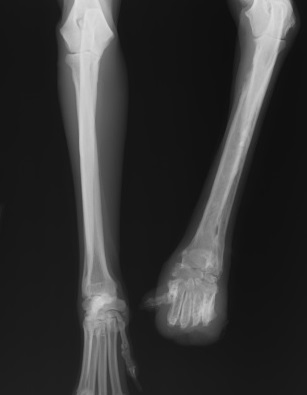

東京で撮ったレントゲンを見て、「状況が非常に悪い」と

骨肉腫の疑いもある。と。

レントゲン画像2

骨肉腫なら肩から切断しても、もう手遅れかもしれない。と。

とりあえずレントゲンを撮って再確認。

結果、骨の状況がすごく良くなっていました。

以前の病院で骨がスカスカな状況はもともとガソリンスタンドで食べてたフードによるもので

保護してから食の改善が進んで、その要因で骨の状況が良くなってきたのではないかということでした。

ここの病院は足の切断は避ける病院でした。

骨の状況が良くなっているのに、切断する必要はない。

という診断を受け、足はとりあえずそのまま残すことになりました。